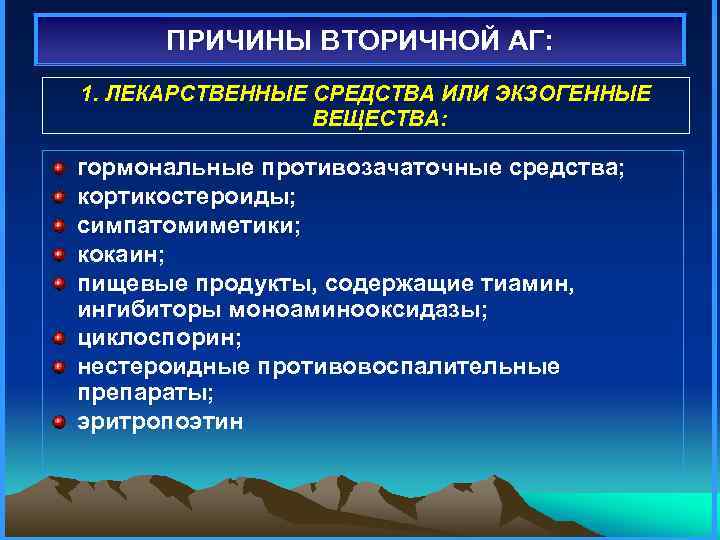

ПРИЧИНЫ ВТОРИЧНОЙ АГ: 1. ЛЕКАРСТВЕННЫЕ СРЕДСТВА ИЛИ ЭКЗОГЕННЫЕ ВЕЩЕСТВА: гормональные противозачаточные средства; кортикостероиды; симпатомиметики; кокаин; пищевые продукты, содержащие тиамин, ингибиторы моноаминооксидазы; циклоспорин; нестероидные противовоспалительные препараты; эритропоэтин

ПРИЧИНЫ ВТОРИЧНОЙ АГ: 1. ЛЕКАРСТВЕННЫЕ СРЕДСТВА ИЛИ ЭКЗОГЕННЫЕ ВЕЩЕСТВА: гормональные противозачаточные средства; кортикостероиды; симпатомиметики; кокаин; пищевые продукты, содержащие тиамин, ингибиторы моноаминооксидазы; циклоспорин; нестероидные противовоспалительные препараты; эритропоэтин